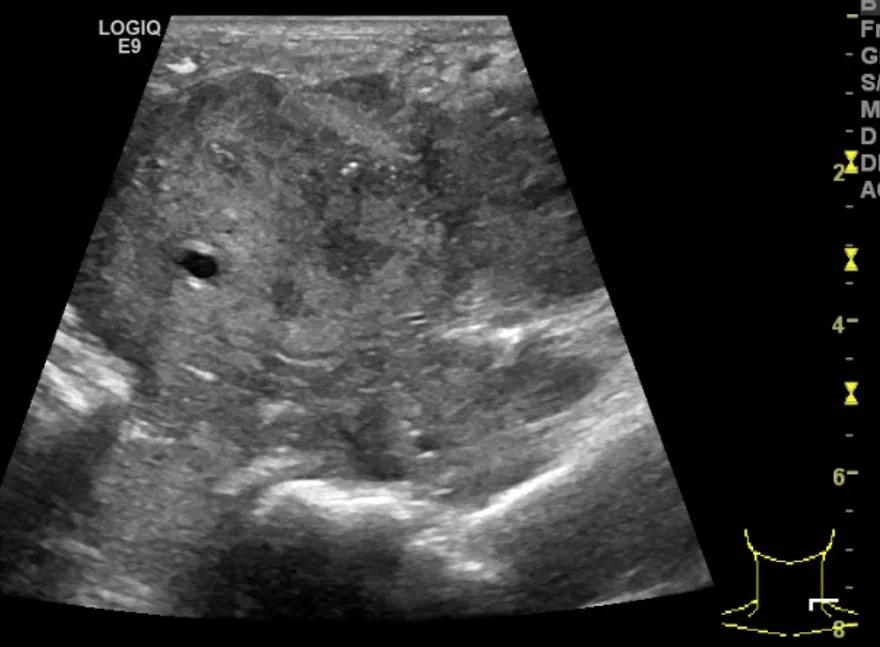

第四例是胸腺癌化妆包,术后、化疗之后淋巴结转移,肿块范围巨大,99mm*61mm,边界不清,呈浸润状,肿块包绕颈动脉,颈内静脉压闭,症状明显。由于患者放化疗也不敏感、血供非常丰富,于是采取多点姑息性消融。姑息性消融后未实现完全消融,病灶大片坏死,肿胀疼痛得到明显的缓解,后续患者未再来复查。

(病例4图例)